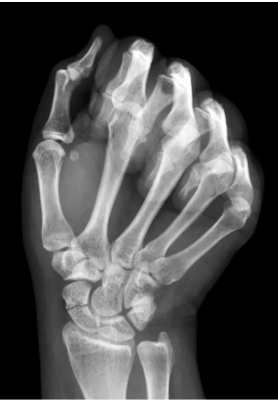

Scaphoid Fractures

Scaphoid fractures are another injury prone to nonunion due to retrograde blood supply, particularly at the waist of the bone. Missed fractures can progress to scaphoid nonunion advanced collapse (SNAC) and post‑traumatic wrist arthritis. Patients often present with anatomic snuffbox tenderness following a fall onto an outstretched hand. Although fractures may be visible on standard three‑view wrist radiographs, MRI is warranted when clinical suspicion remains high despite negative x‑rays. Immobilization in a thumb spica splint and referral to a hand specialist are essential.